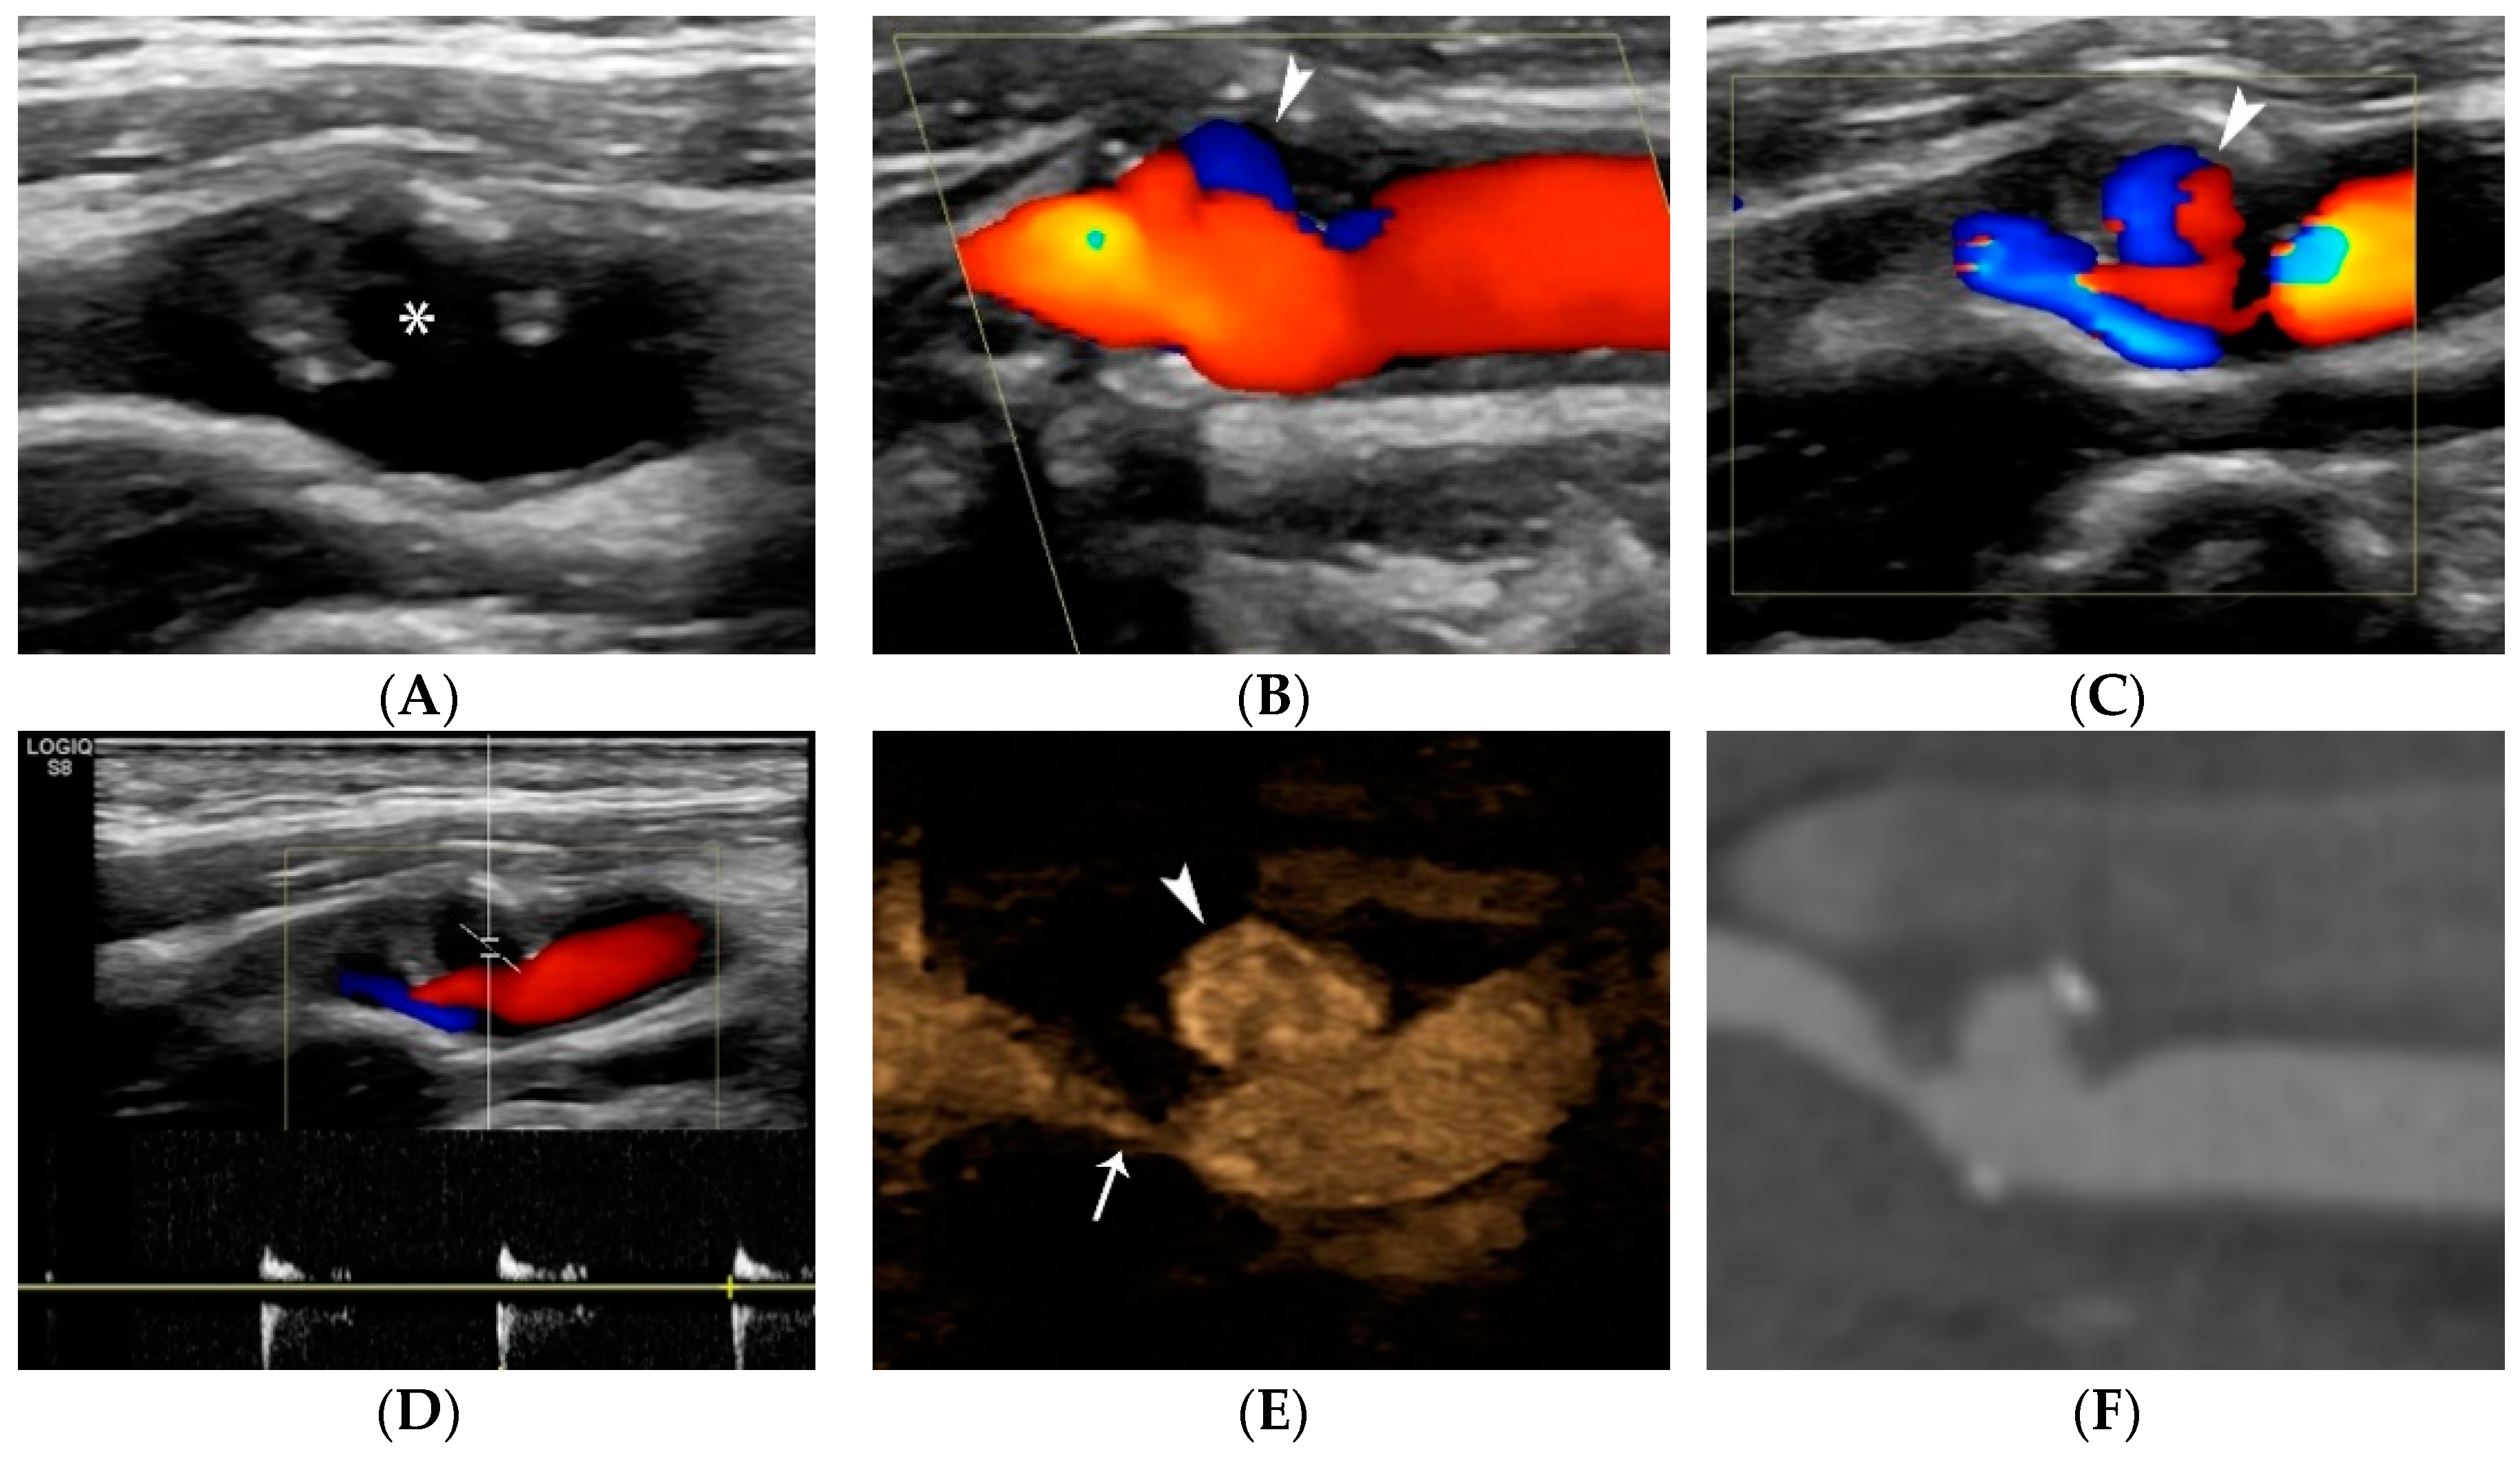

4.1.4. Plaque Ulceration

- Rafailidis, V.; Chryssogonidis, I.; Tegos, T.; Kouskouras, K.; Charitanti-Kouridou, A. Imaging of the ulcerated carotid atherosclerotic plaque: A review of the literature. Insights Imaging 2017, 8, 213–225. [Google Scholar] [CrossRef]

- Hamada, O.; Sakata, N.; Ogata, T.; Shimada, H.; Inoue, T. Contrast-enhanced ultrasonography for detecting histological carotid plaque rupture: Quantitative analysis of ulcer. Int. J. Stroke 2016, 11, 791–798. [Google Scholar] [CrossRef] [PubMed]

- ten Kate, G.L.; van Dijk, A.C.; van den Oord, S.C.; Hussain, B.; Verhagen, H.J.; Sijbrands, E.J.; van der Steen, A.F.; van der Lugt, A.; Schinkel, A.F. Usefulness of contrast-enhanced ultrasound for detection of carotid plaque ulceration in patients with symptomatic carotid atherosclerosis. Am. J. Cardiol. 2013, 112, 292–298. [Google Scholar] [CrossRef] [PubMed]

- Saha, S.A.; Gourineni, V.; Feinstein, S.B. The Use of Contrast-enhanced Ultrasonography for Imaging of Carotid Atherosclerotic Plaques: Current Evidence, Future Directions. Neuroimaging Clin. N. Am. 2016, 26, 81–96. [Google Scholar] [CrossRef] [PubMed]

- Rafailidis, V.; Charitanti, A.; Tegos, T.; Rafailidis, D.; Chryssogonidis, I. Swirling of microbubbles: Demonstration of a new finding of carotid plaque ulceration on contrast-enhanced ultrasound explaining the arterio-arterial embolism mechanism. Clin. Hemorheol. Microcirc. 2016, 64, 245–250. [Google Scholar] [CrossRef]

- Rafailidis, V.; Chryssogonidis, I.; Xerras, C.; Nikolaou, I.; Tegos, T.; Kouskouras, K.; Rafailidis, D.; Charitanti-Kouridou, A. A comparative study of color Doppler imaging and contrast-enhanced ultrasound for the detection of ulceration in patients with carotid atherosclerotic disease. Eur. Radiol. 2019, 29, 2137–2145. [Google Scholar] [CrossRef]

- Lyu, Q.; Tian, X.; Ding, Y.; Yan, Y.; Huang, Y.; Zhou, P.; Hui, P. Evaluation of Carotid Plaque Rupture and Neovascularization by Contrast-Enhanced Ultrasound Imaging: An Exploratory Study Based on Histopathology. Transl. Stroke Res. 2021, 12, 49–56. [Google Scholar] [CrossRef]